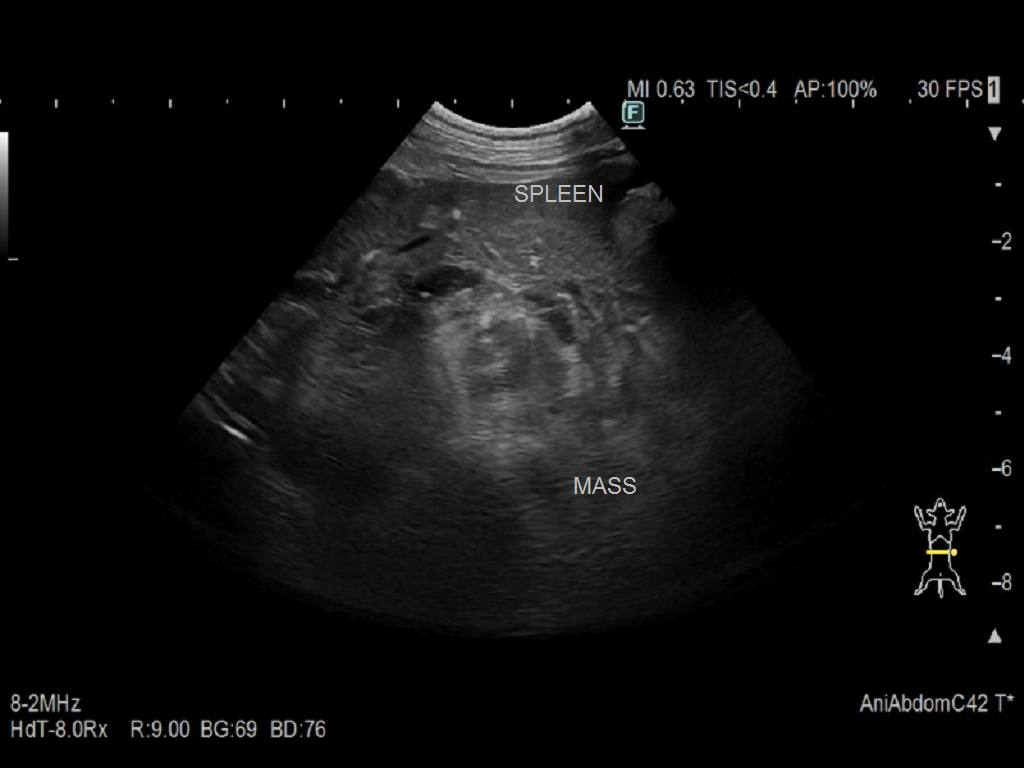

身体検査:粘膜蒼白、腹部膨満 血液検査:貧血(PCV 20%)、凝固異常(PT延長、APTT延長) 画像検査: ・X線検査:腹水の貯留が認められた。 ・腹部超音波:脾臓に多発性の低エコー性病変を認めた(図1)。多量の腹水を確認した(図2)。超音波ガイド下で腹腔穿刺を実施し、血様液を採取した。診断